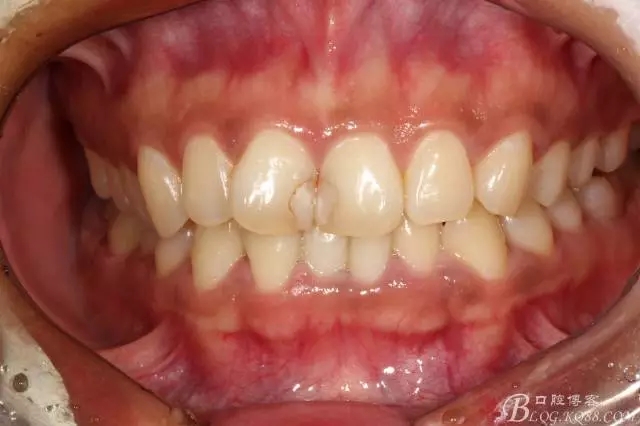

粘接完成即刻照

即刻照局部放大

兩周后復(fù)查(訴11遇冷有點(diǎn)不適,因11備牙有點(diǎn)多,露牙本質(zhì)。囑注意不要進(jìn)食過(guò)冷過(guò)熱食物。癥狀約一個(gè)月后逐漸消失。)

半年后(2016.9)復(fù)查照(這次復(fù)查已完全適應(yīng)修復(fù)后的效果,冷熱也不敏感了,我的心也就放下了)